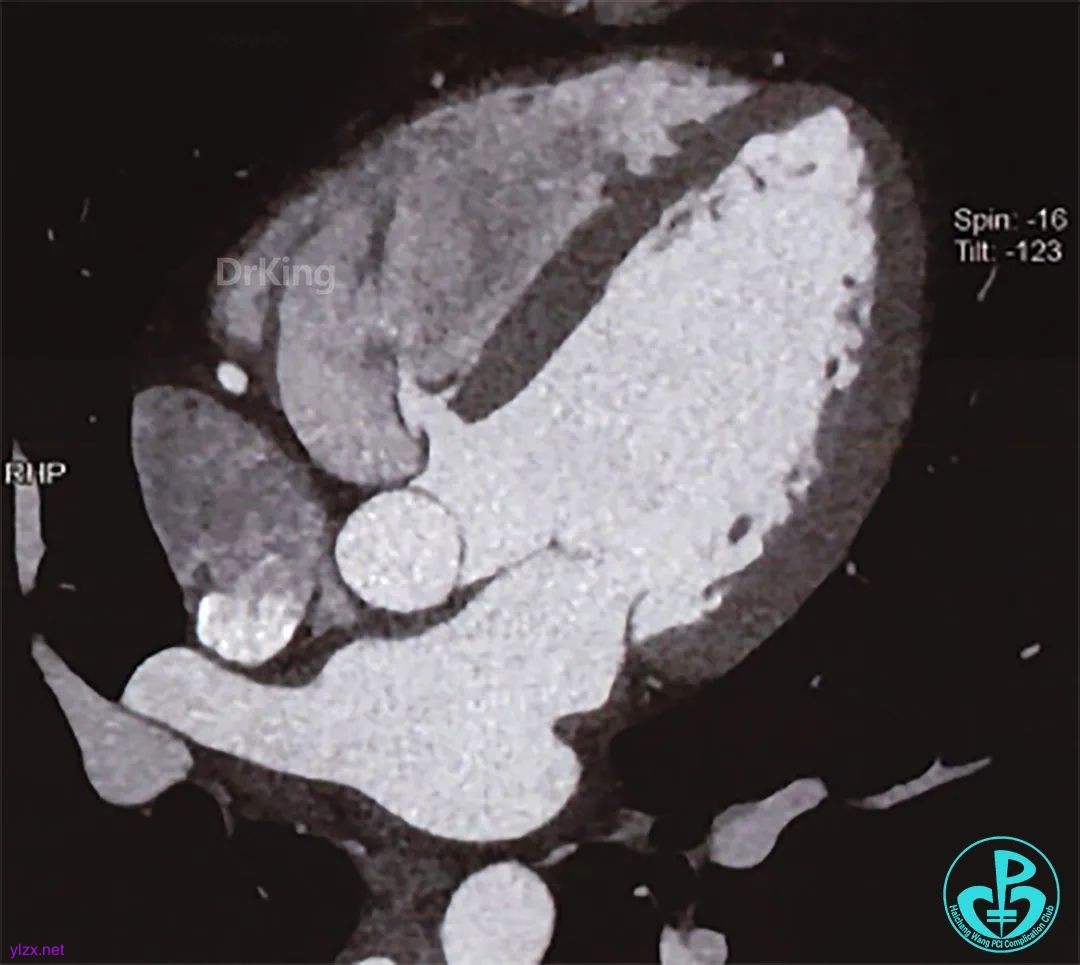

术前CT全方位判断室缺位置、形态及大小: